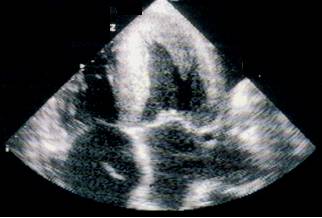

Ecocardiografia permite evaluarea afectarii functiei contractile, excluderea unor boli valvulare sau pericardice. Se apreciaza forma si functia VS (tipic VS globulos cu functie contractila global alterata), gradul insuficientelor valvulare, prezenta trombozei intracavitare (intraatriala sau intraventriculara). Cresterea dimensiunilor cavitatilor stangi si drepte este progresiva cu cresterea clasei functionale NYHA. Producerea emboliilor se asociaza cu dimensiunea VS si fractia de ejectie (FE).

-Ecocardiografia demonstreaza un grad de disfunctie VS - adesea regionala, sau kinetica poate fi normala. Se pot intalni pereti ingrosati, trombi VS, functie diastolica (umplere diastolica) anormala.